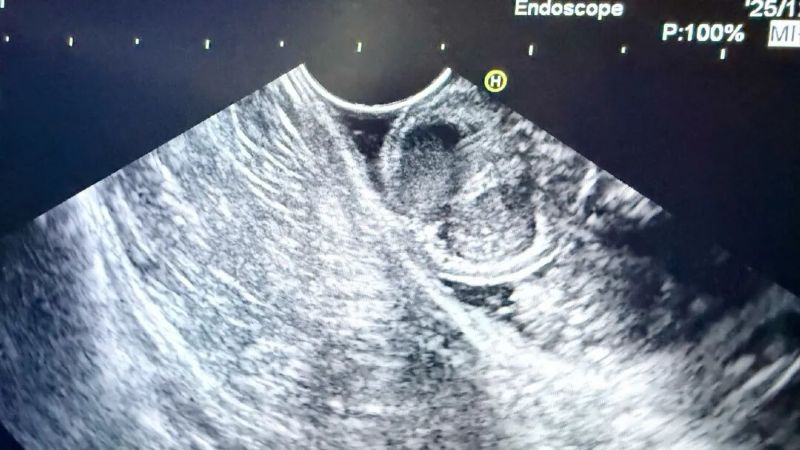

為進(jìn)一步明確病變性質(zhì)與起源層次,消化內(nèi)科二病區(qū)張榮主任團(tuán)隊(duì)為患者安排了增強(qiáng)CT、超聲內(nèi)鏡等一系列精密檢查。完善上述檢查后,結(jié)合影像學(xué)特征考慮良性病變可能性大,但仍無(wú)法完全排除惡性可能,病變性質(zhì)的最終判定,必須依靠完整切除標(biāo)本后的病理診斷。

患者超聲內(nèi)鏡以及胃鏡圖